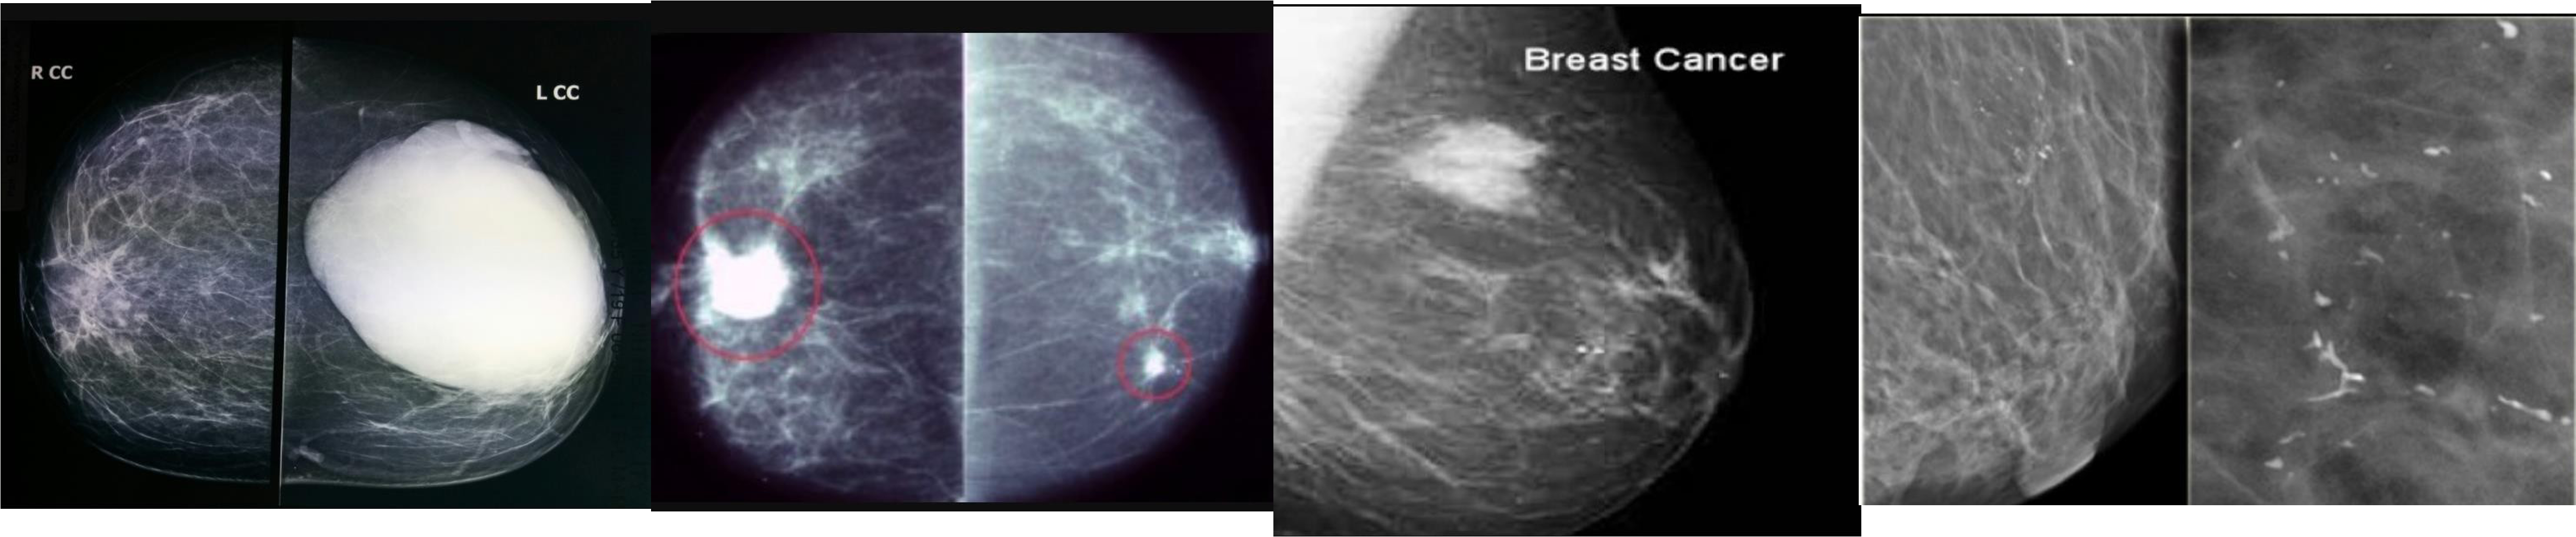

MAMMOGRAM

fibroadenoma